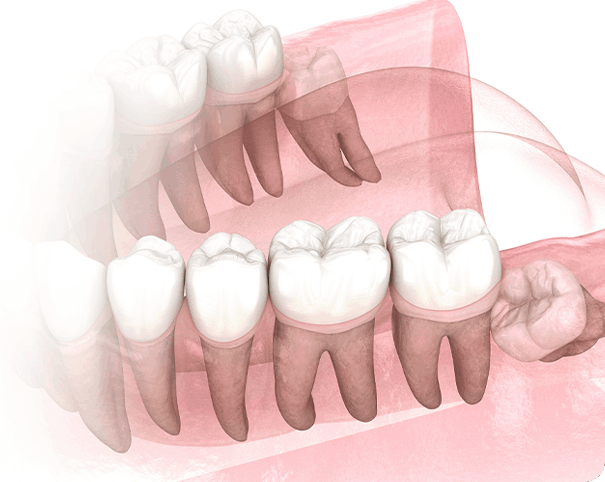

사랑니가 반듯하게 나서 씹는 기능을 할 수 있다면 굳이 뽑지 않아도 됩니다.

하지만 잇몸에 매복된 채 자라나는 사랑니는 구강관리가 어려워 인접 치아에 충치와 염증을 쉽게 불러일으킬 수 있습니다.

이를 방치할 경우 병변 부위가 넓어지면서 치료 비용과 기간이 높아지고 사랑니 뿌리와 잇몸뼈가

단단히 유착되어 발치하는 것이 매우 어려워 집니다.

잇몸과 뼈에 붙어있던 사랑니가 어금니를 흡수시켜 어금니를 사용할 수 없게 만듭니다.

치주인대가 퇴화되면서 사랑니 뿌리와 잇몸뼈가 유착되면 발치가 매우 어려워져 부작용의 위험이 높아집니다.